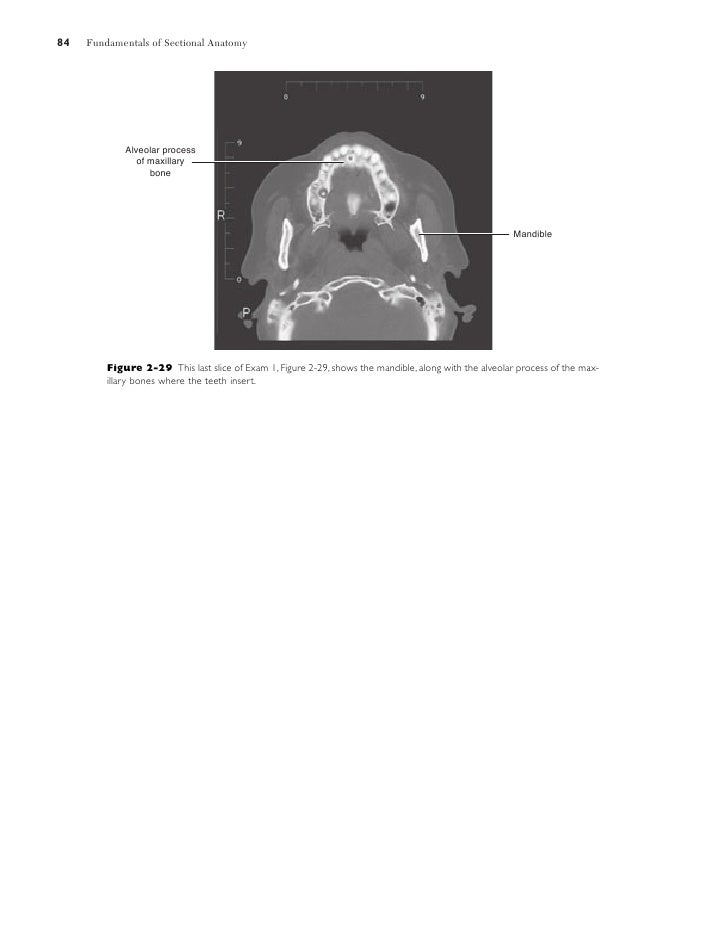

Sectional Anatomy